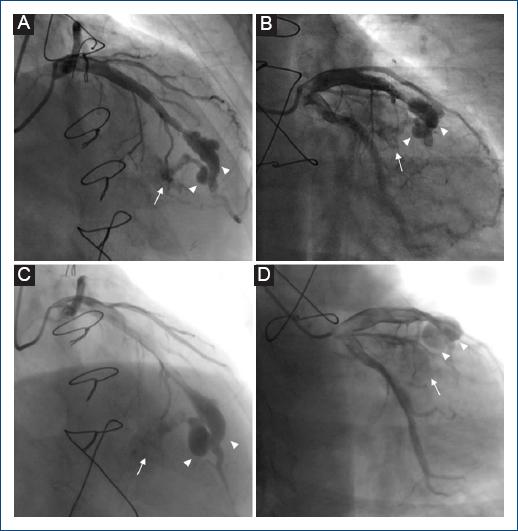

Entre los años 2013 y 2018 se realizaron siete BEM con el mismo resultado patológico de la primera biopsia, sin complicaciones durante la intervención. Asimismo, en 2017 se realizó nueva ACI (Fig. 2 A B). En el año 2023 se realizó nueva BEM y ACI de rutina (Fig. 2 C D). La ecocardiografía transtorácica no logró determinar derivación izquierda-derecha significativa, con tamaño de cavidades cardiacas dentro del rango de normalidad y adecuada función biventricular.

Figura 2 A y B: angiografía coronaria invasiva (ACI) en el año 2017. Aneurismas (puntas de flecha) de dimensiones 20.6 x 7.6 mm y 7.2 x 4.5 mm sobre arteria descendente anterior y fístula coronaria (flecha) que comunica sus ramos septales con el ventrículo derecho. C y D: angiografía coronaria invasiva (ACI) en el año 2023. Aneurismas (puntas de flecha) de dimensiones 21.5 x 7.9 mm y 14.9 x 8.8 mm sobre arteria descendente anterior y fístula coronaria (flecha) que comunica sus ramos septales con el ventrículo derecho.